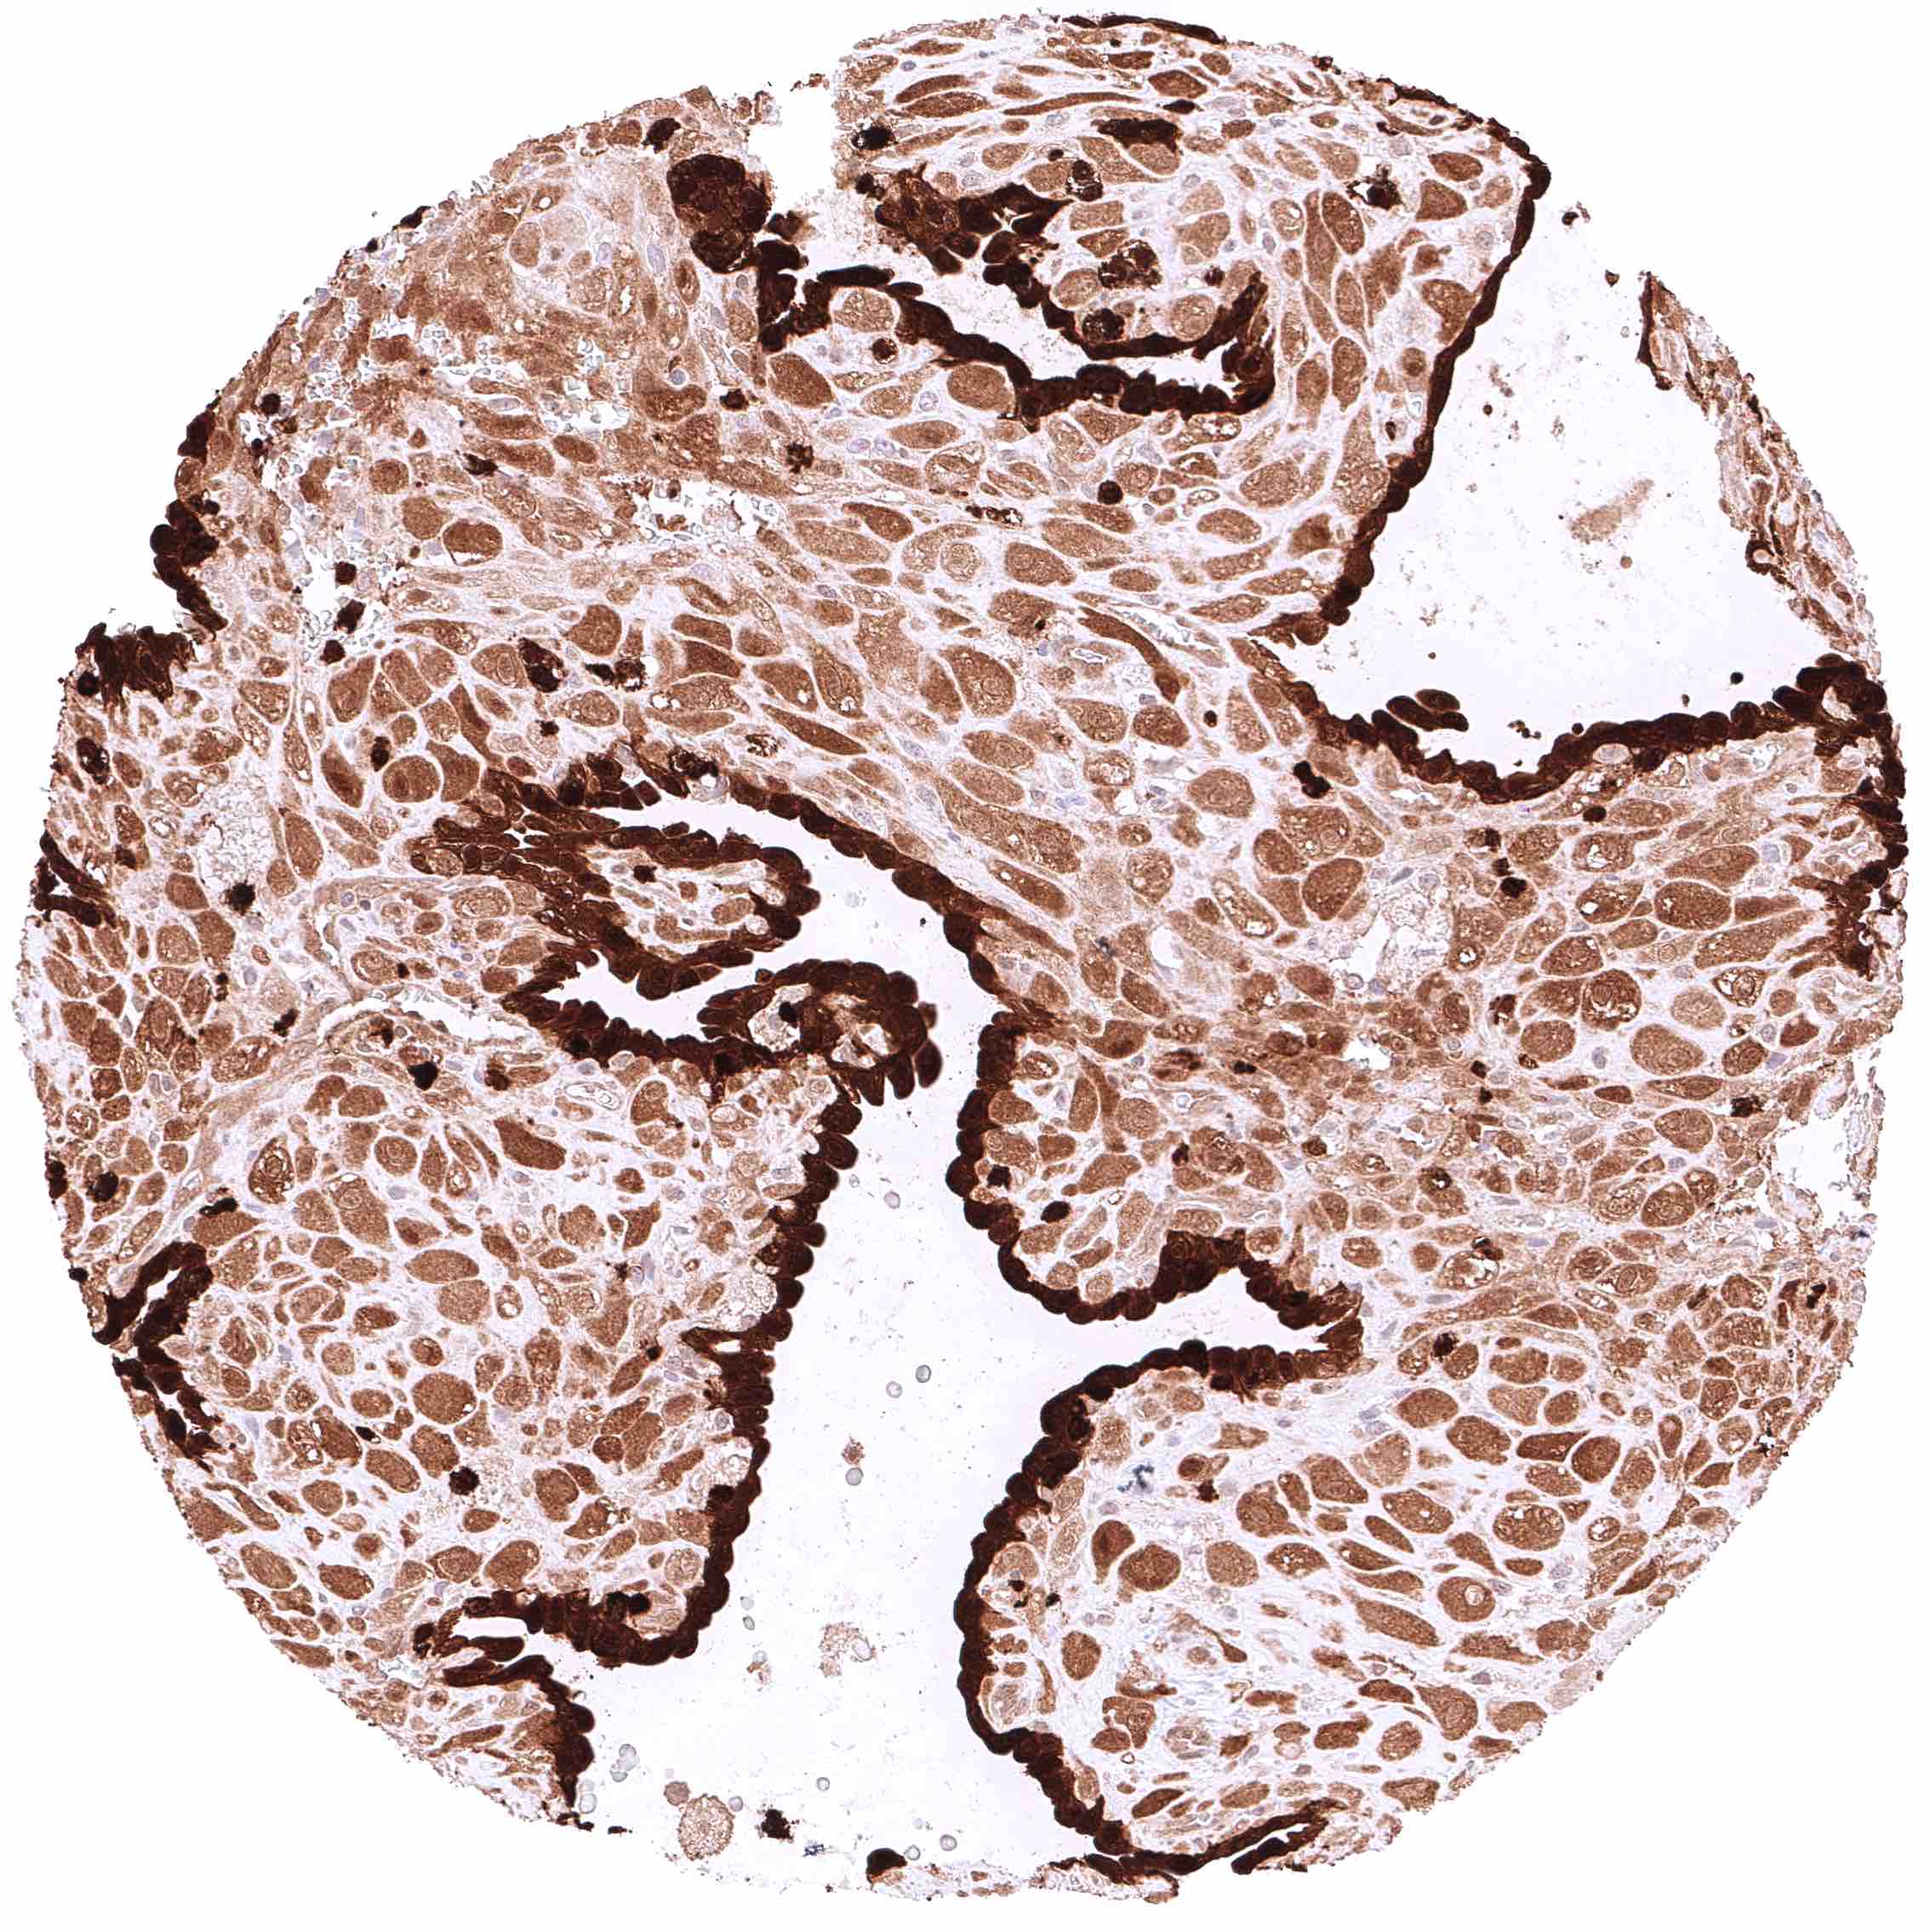

Esophagus, squamous epithelium – Strong cytoplasmic and nuclear GSTP1 positivity of squamous epithelial cells. Staining intensity is highest in the basal and suprabasal cell layers and decreases slightly towards the surface